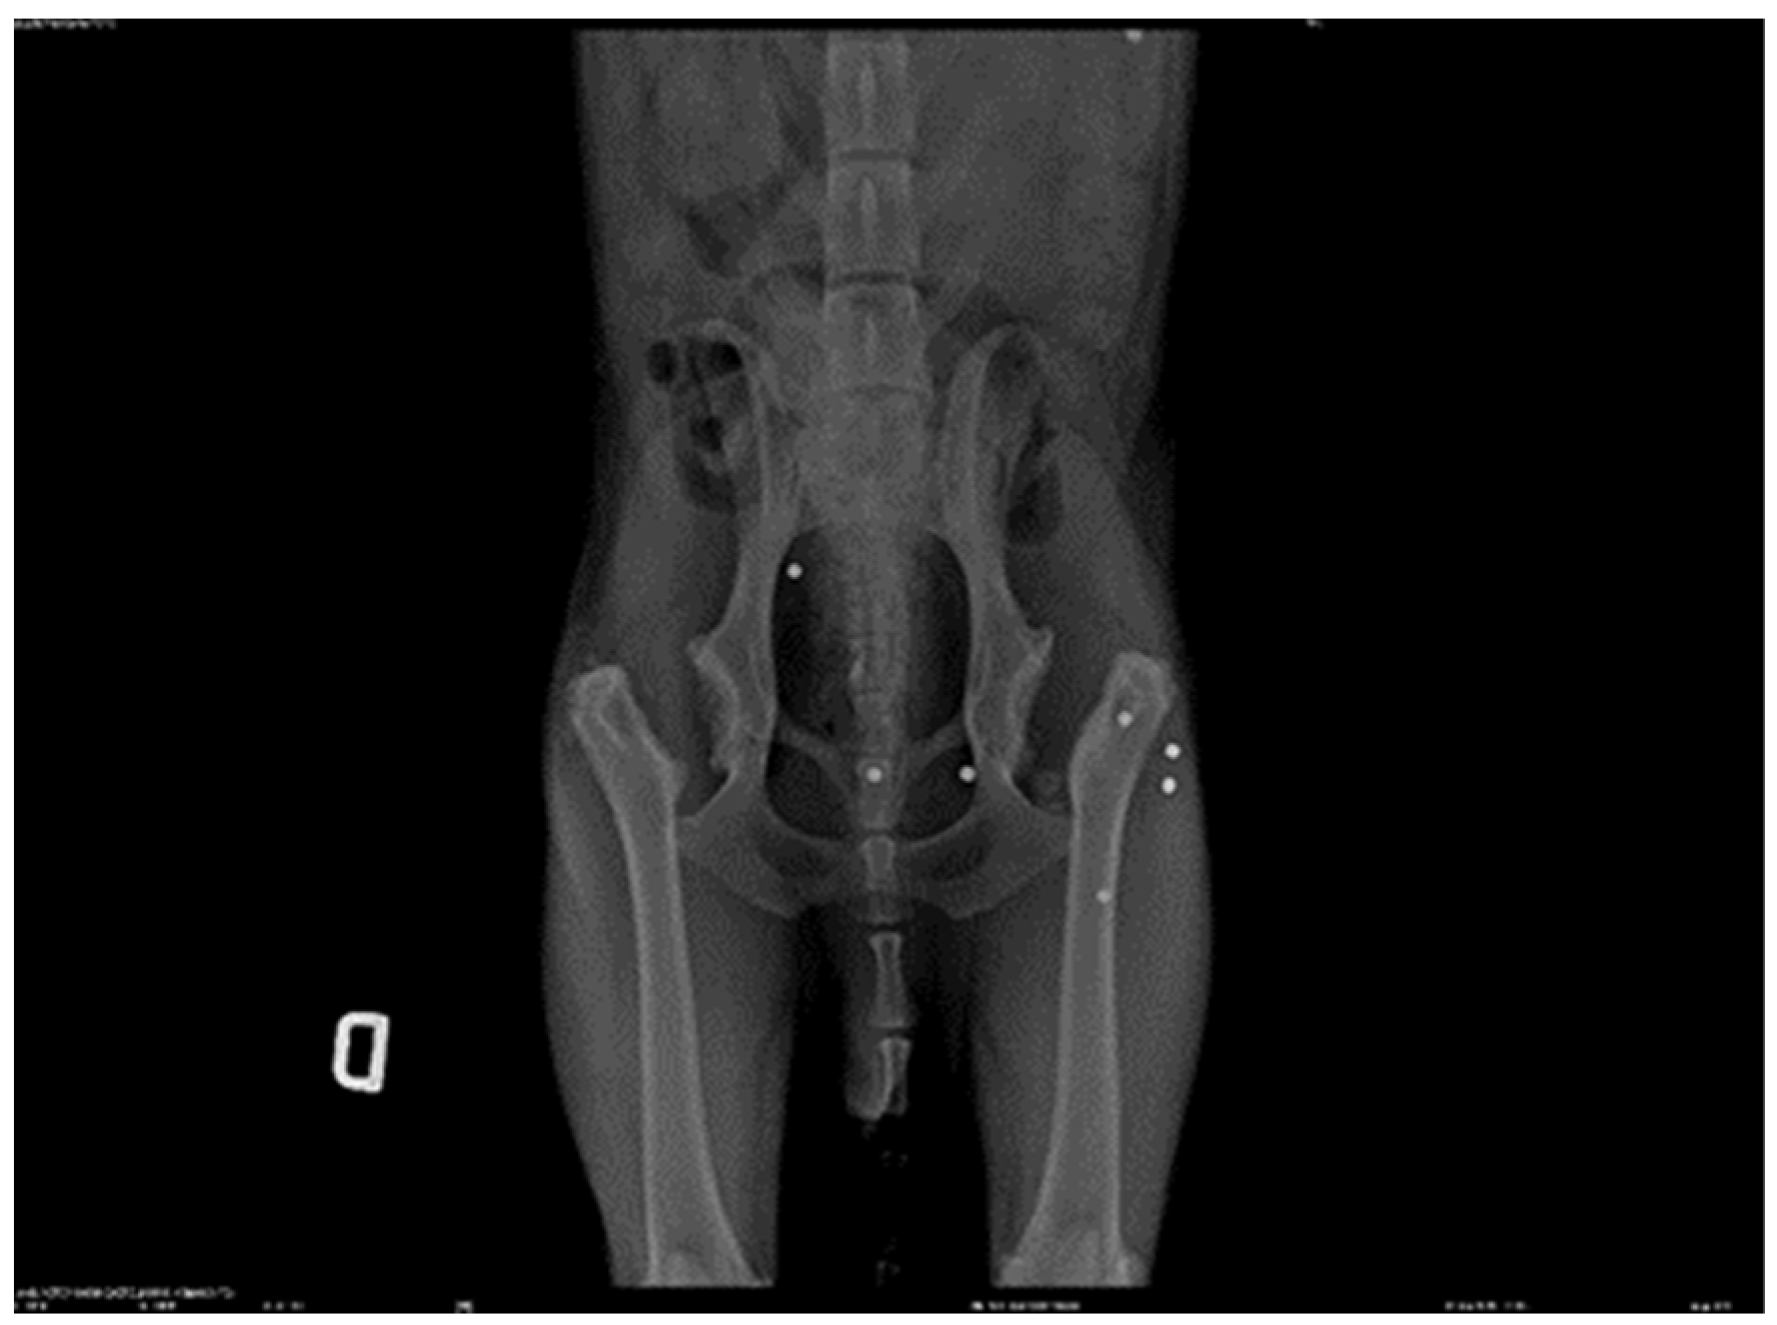

2.1. Patient Details a 7-Year-Old Male Canine Setter, 23 kg Was the Subject of This Study

2.3. Assessment

3. Results